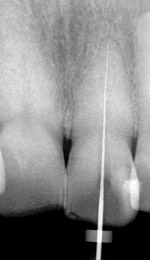

Fig. 7 Gouging typical of round bur-driven, cingulum-positioned access, likely compounded by insufficient magnification.

Figure 7